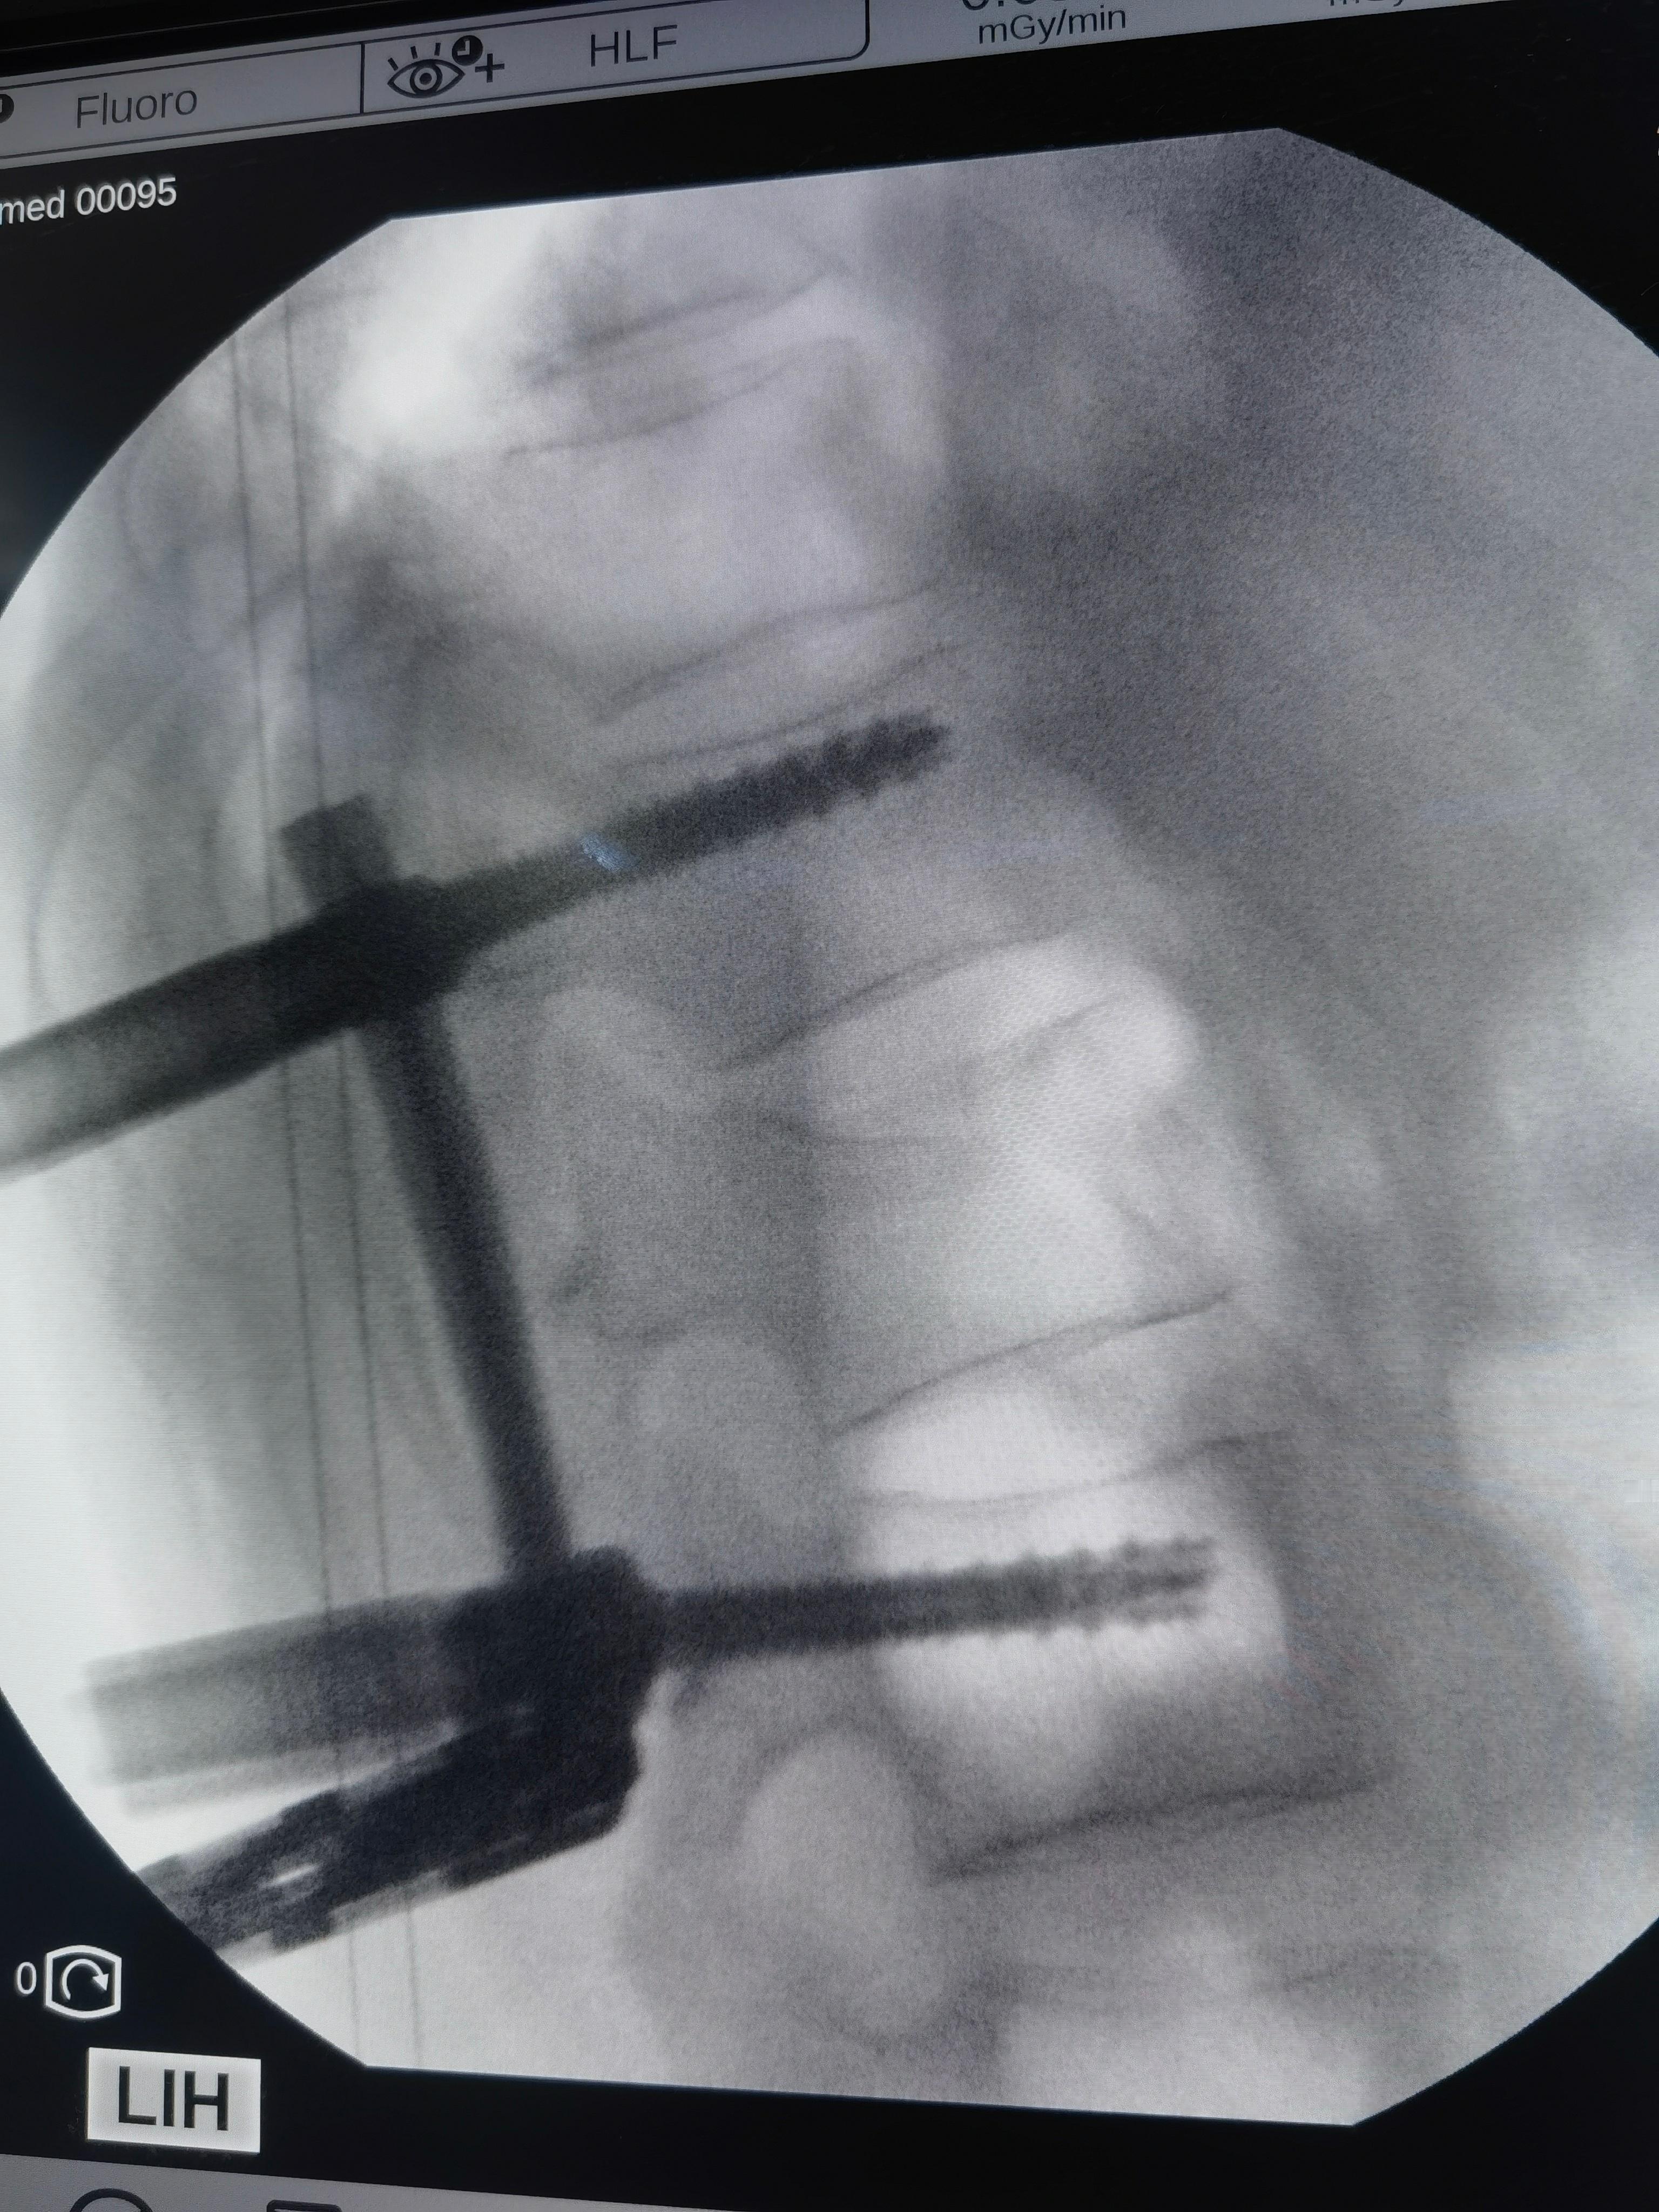

确诊为脆皮年轻人:小伙子今年41岁,参加公司团建去泰国玩儿。小船出海,风大浪大,几个颠簸,骨折,剧痛,只能躺着。同事三个人,两个骨折,另一个轻一点儿,去协和康复科保守治疗。我帮小伙子做了微创钉棒手术,4个小孔,完美复位固定。手术中发现骨头的确不行,类似60多岁女性。这种冻豆腐骨头,不建议保守治疗,越躺越疏松。脆皮天天见,天天坐班,下班躺床上刷手机,缺乏锻炼。。。大家一定要小心,可能是你,也可能是我。休假要去滑雪啥的,把保险买好。[笑cry]